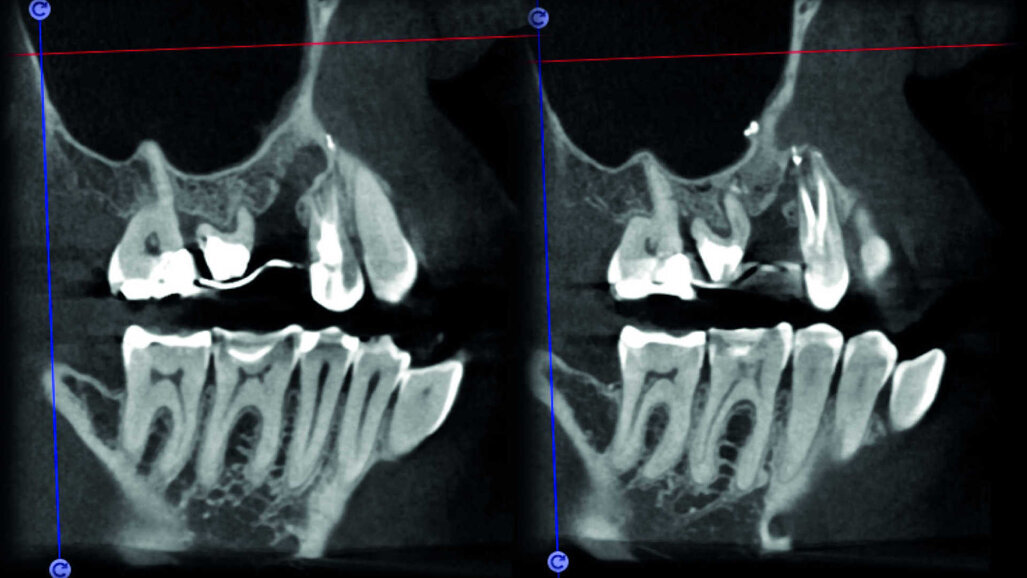

Le cas avec lequel je souhaite commencer mon exposé clinique est un exemple parfait de la difficulté à définir l’origine des symptômes d’un patient, par l’examen d’une simple radiographie intraorale. Non seulement l’examen 2D ne permet pas d’établir avec certitude la présence d’une lésion, mais surtout, il est impossible d’en déterminer la taille, la morphologie et le type. Au contraire, une analyse de l’imagerie 3D offre une image claire de la situation clinique. Chez ce patient, les coupes coronales et sagittales révèlent la présence d’une importante lésion s’étendant de l’apex de la racine mésiale de cette molaire jusqu’à la zone de furcation, tandis que les coupes axiales nous permettent d’analyser précisément l’anatomie endodontique et, en particulier, la forme de la racine mésiale, qui apparaît fusionnée avec la racine palatine. Un panorama complet du cas peut donc guider le processus de décision et orienter le plan de traitement vers une modalité bien précise de traitement (Figs. 1–4).